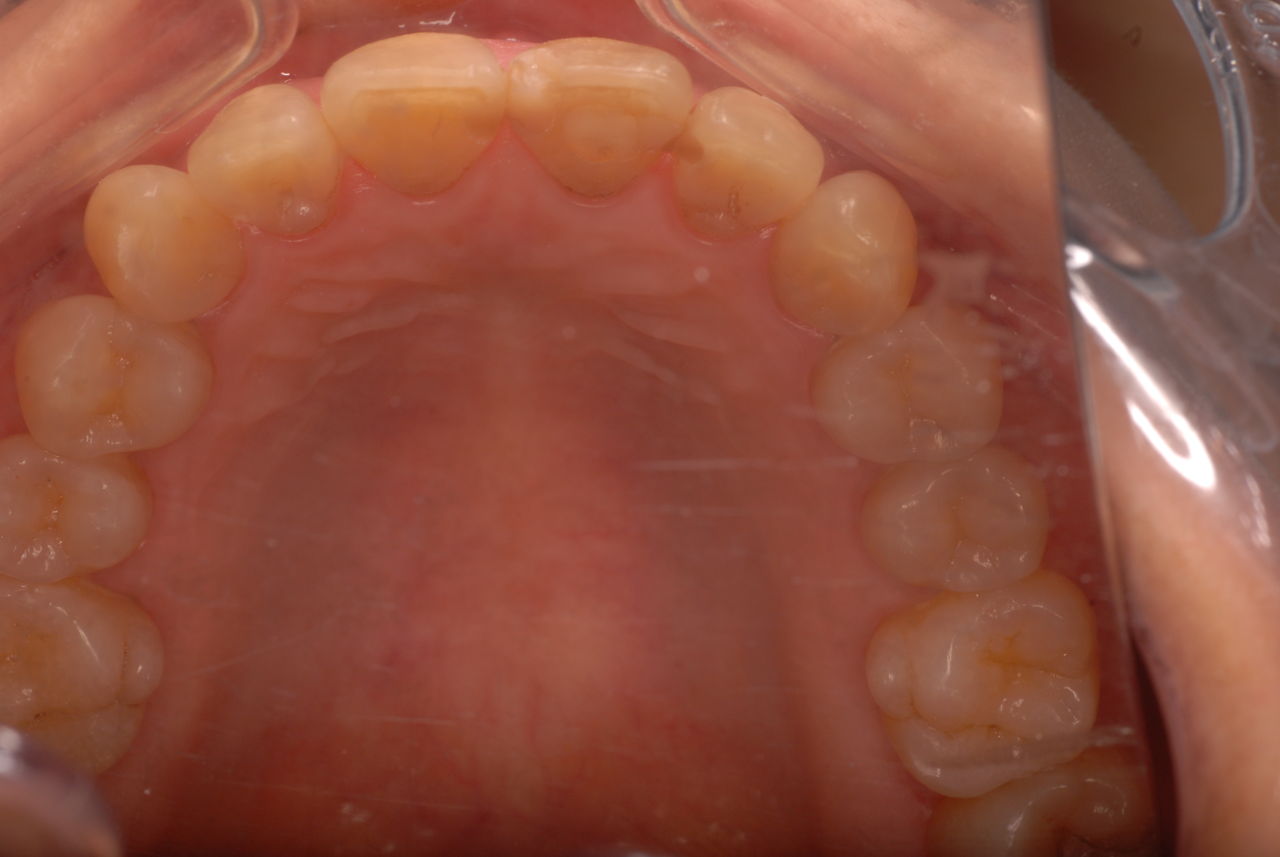

14年歯前、歯の神経が腐り、神経を除去したまま来なくなった現在大学生の女性

歯周病になっていましたが、少し色が黄色くなっているだけで比較的綺麗な歯の状態です。

平成9年来院神経を取り、同時に歯周病の話をしてそのまま来なくなっていたかたですが、たまたま一部欠けてきました。それで来院。

虫歯という病気を完全に治し、神経の処置で神経の病気を治し、ブラシの使い方をマスターすれば歯やお口の中は問題を起こしにくいのです。何かを被せることは注意が必要ですし、歯を傷つける訳ですからブラシの使い方をマスターしてから被せないと危ないのです。